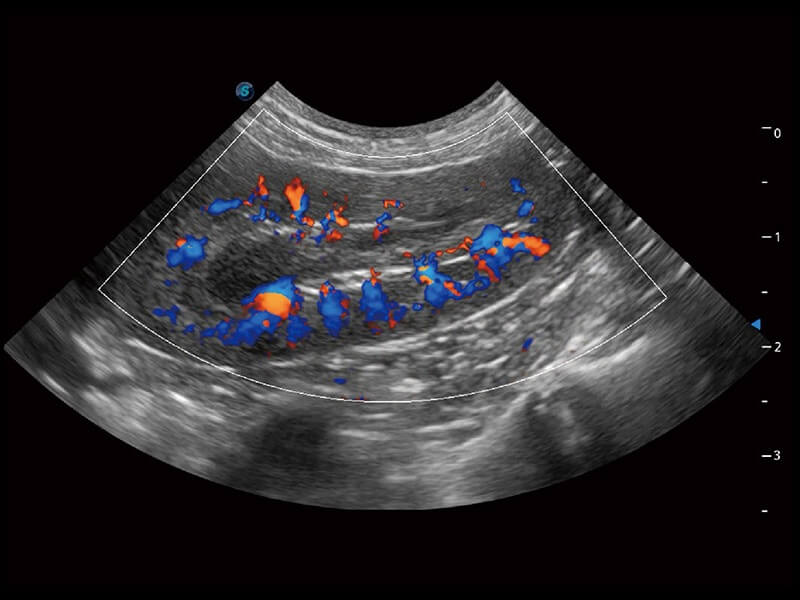

ProPet 60 作为一款高端台式动物超声设备,为动物医生的日常诊断提供了一系列贴合动物临床需求、解决临床实际问题的高级成像功能。凭借全系列高清探头,满足医生对腹部、心脏、生殖、浅表、肌骨等成像的所有需求,切实帮助您提升检查效率,提高诊断信心。

兽用彩色多普勒超声诊断系统